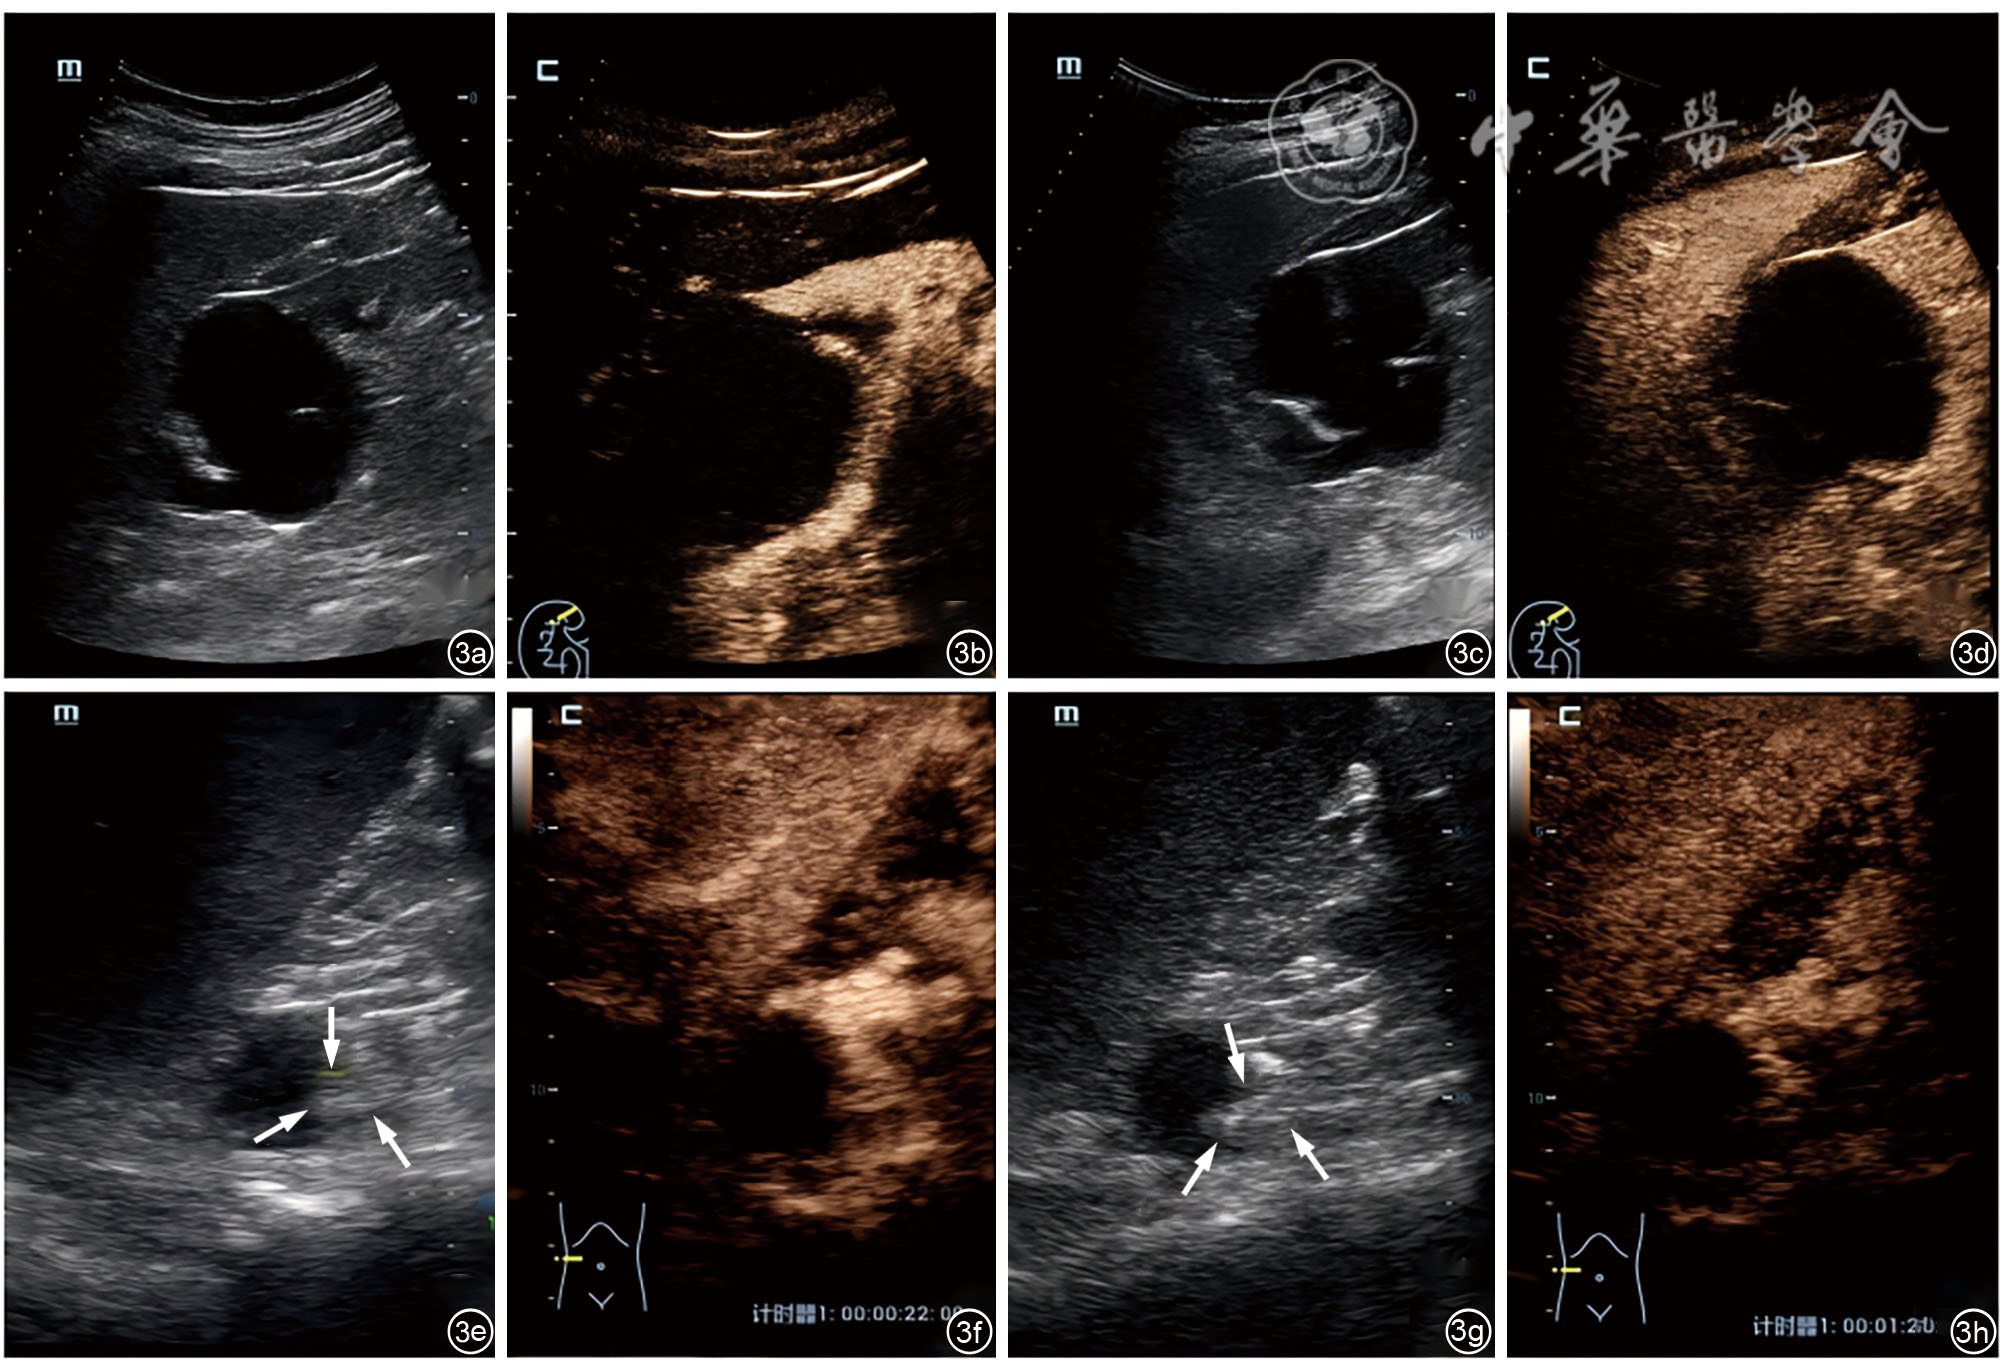

图3 与常规超声Bosniak分级相比超声造影分级降级的肾脏囊性病变声像图表现。图a~d示右肾上极囊性病灶,常规超声(图a、c)可见囊内有5条分隔(>4条),且最厚的分隔厚度>3 mm,根据常规超声Bosniak分级应分为Ⅲ级;而超声造影(图b、d)可见囊内有1条纤细(厚度<2 mm)分隔,根据超声造影Bosniak分级应将其降至Ⅱ级,术后病理结果提示为良性囊肿。图e~h示右肾上极囊性病灶,常规超声(图e、g)显示病灶囊壁上可见壁结节(箭头所示),根据常规超声Bosniak分级应分为Ⅳ级;而超声造影显示病灶囊壁稍增厚(厚度<2 mm),且囊内未见壁结节,根据超声造影Bosniak分级应将其降至Ⅱ级,术后病理结果提示为单纯性肾囊肿